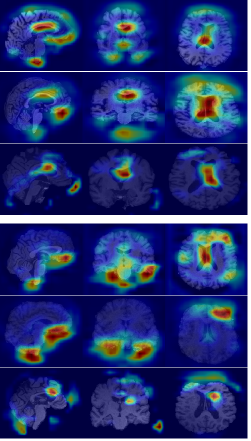

Refer to caption

(a)

(b)

(c)

Figure 6: Grad-CAM visualizations on MRI scans from ADNI and AIBL datasets. (a) Input images for NC, MCI, and AD groups. (b) Attention maps from the model without morphological modules. (c) Attention maps with morphological modules, showing improved focus on disease-relevant regions.

From a qualitative standpoint, Fig. 6 further presents Grad-CAM visualizations comparing the baseline 3D U-Net model and the proposed pseudo-morphological modules for AD detection. The leftmost column shows original MRI slices from both ADNI and AIBL datasets across three classes: NC, MCI, AD. The middle column illustrates attention maps generated by the baseline U-Net3D model, which are less focused, suggesting limited class-specific feature localization. In contrast, the rightmost column shows Grad-CAM results from the model enhanced with pseudo-morphological modules. These attention maps are more focused on areas in the brain which are known to be affected by AD, such as the hippocampus and surrounding medial temporal lobe. This indicates that incorporating class-specific morphological augmentations helps the model learn more discriminative and generalizable features for AD detection.